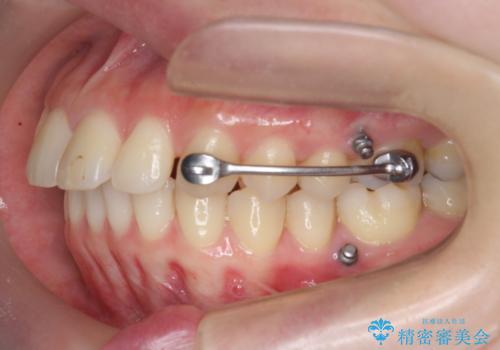

カリエール・マイクロインプラントを用い、時間はかかりましたが大きく歯の後方移動が達成され、前歯の見た目が大きく改善されました。

大きな後方移動を達成するにはマイクロインプラントと日常的なゴムかけが大切です。